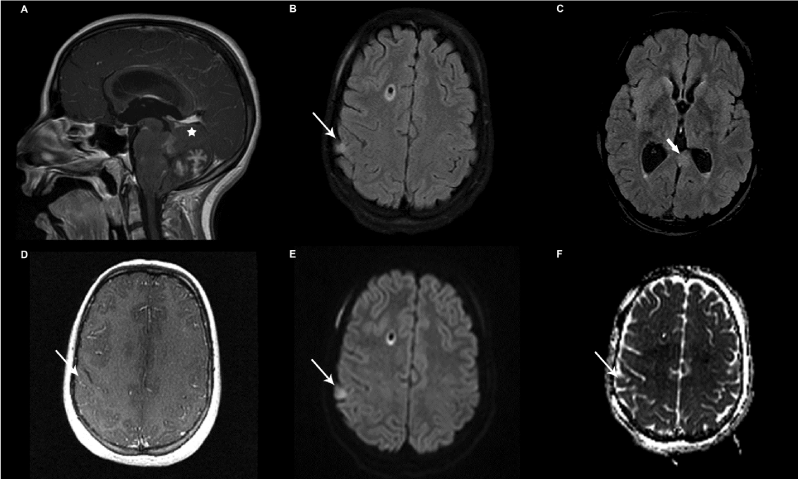

| Figure 1: Images from the MRI study at presentation showing the enhancing posterior fossa medulloblastoma (A- white asterisk). Axial FLAIR images demonstrating the hyperintense right parietal lesion considered a parenchymal metastatic deposit (B-thin white arrow) and left medial temporal lesion (C–thick white arrow). No enhancement is seen in the right parietal lesion (D-thin white arrow). B=1000 diffusion image (E) and corresponding ADC map (F) demonstrating restricted diffusion in the right parietal lesion (thin white arrow). |